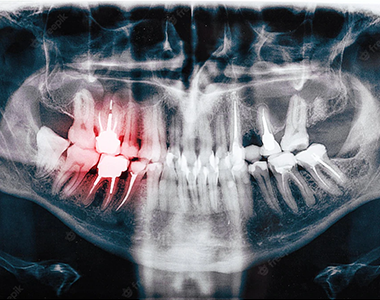

Dental X-rays offer a detailed view of the health of your teeth, gums, and jawbone that isn’t visible during a regular dental exam. Early tooth decay, infections in the root, and bone loss around teeth often don’t present obvious signs. X-rays can reveal these issues before they become more serious problems, helping us to address them early and effectively.

For children, X-rays are used to monitor the development of adult teeth and assess when they will emerge. In adults, X-rays help in evaluating the alignment of wisdom teeth and identifying any potential issues before they cause complications.

Dental X-rays can reveal issues not visible during a routine examination, such as:

• Decay: Hidden decay beneath fillings or between teeth.

• Infections: Root infections and their severity.

• Teeth Development: In children, it shows emerging adult teeth and space availability.

• Wisdom Teeth: For adults, it identifies impacted wisdom teeth that may require removal.